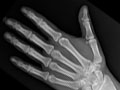

An extremity X-ray is a picture of your hand, wrist, arm, foot, ankle, knee, hip, or leg. It is done to see whether a bone has been fractured or a joint dislocated. It is also used to check for an injury or damage from conditions such as an infection, arthritis, bone growths (tumors), or other bone diseases, such as osteoporosis.

X-rays are a form of radiation, like light or radio waves, that are focused into a beam, much like a flashlight beam. X-rays can pass through most objects, including the human body. X-rays make a picture by striking a detector that either exposes a film or sends the picture to a computer. Dense tissues in the body, such as bones, block (absorb) many of the X-rays and look white on an X-ray picture. Less dense tissues, such as muscles and organs, block fewer of the X-rays (more of the X-rays pass through) and look like shades of gray on an X-ray. X-rays that pass only through air, such as through the lungs, look black on the picture.